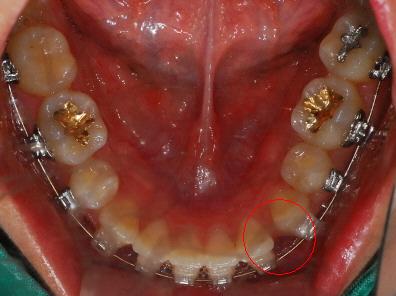

치과에 다녀왔습니다. 벌써 25번째 치아교정후기네요ㅎㅎㅎ 먼저 치아 사진을 보시면 아랫니에 공간이 살짝 생긴 것이 보이는 데요

<하악사진> 저는 처음에 왜 다시 벌어지지? 하고 걱정했는데 치과선생님께서 벌리는 것이 더 어렵다고 하셨어요~ 의도된 과정이었더라구요*^^* 이번달은 고무줄을 다시! 이용하여 윗니는 뒤로 아랫니는 앞으로 당겨주는 작업을 할거에요 그래서 고무줄은 위아래로 걸게 되었습니다~ 밥먹을 때 마다 뺏다 꼈다 해야 하는데 오랜만에 다시 고무줄끼니 정말....아프네요 맛잇는거 있어도 못먹고.. 옛날에 엄마가 치아가 많이 빠져서 딱딱한거 먹는 저랑 동생들 보면서 밥먹을때마다 부럽다고 하셨었는데 지금 제가 그러니 진짜 부럽고.. 엄마께 미안한 마음도 들고 그래요..ㅠㅠ

아아 쨋든 이번달 과정은 고무줄이구요 한가지 더~ 윗니가 예전사진을 보면 앞니 뒤가 많이 울퉁불퉁 한 것을 볼 수 있는데요 윗니와 아랫니가 서로 좀 더 가깝게 하기 위해 뒷부분을 좀 깎는 작업을 했습니다 치과쌤의 표현 방식을 빌리면 일종의 배가 나온 부분을 다이어트 시켰다고나 할까요?!ㅎㅎㅎㅎ (내 배도좀 해야될듯....)